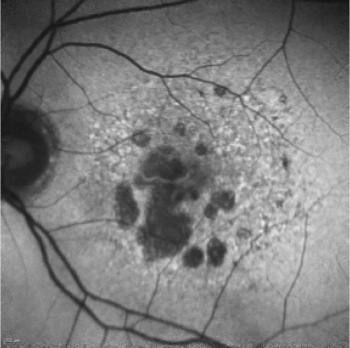

The first approved GA treatment leaves room for additional therapies.